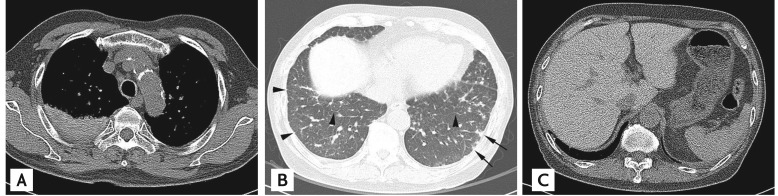

Figure 1

A 74-year-old female with amiodarone pulmonary toxicity (APT) exhibiting a pulmonary interstitial fibrosis pattern. Computed tomography (CT) scans obtained at the level of both lower lobes revealed intralobular and interlobular septal thickenings in the peripheral regions of both lower lobes (arrowheads), and interlobular septal thickenings in the central and middle regions of the right lower lobe (arrows). The APT CT score was 4 on this CT section; the involved regions included the central, middle, and peripheral regions.